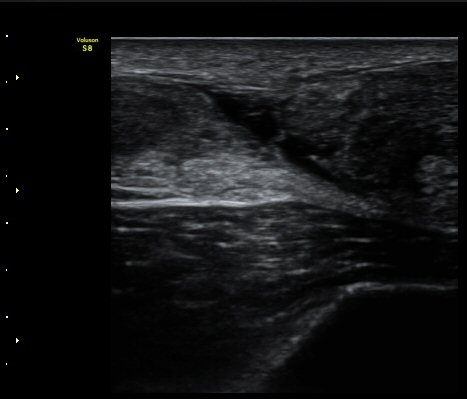

[¹ß¸ñ] ¾ÆÅ³·¹½º ÈûÁÙ ÆÄ¿­ÀÇ ÃÊÀ½ÆÄ Áø´Ü

ÁÂÃø ¹ß¸ñÀÇ ÅëÁõ(2ÁÖ)

2ÁÖ Àü ¹èµå¹ÎÅÏÇÏ´Ù°¡ ¹ß¸ñÀÇ ÅëÁõÀÌ ¹ß»ýÇÏ¿© Ÿº´¿ø¿¡¼­ ÃÊÀ½ÆÄ°Ë»ç µî ½ÃÇàÇÏ°í ºÎ¸ñ°íÁ¤ ÈÄ ¹°¸®Ä¡·á À§ÇØ ³»¿ø

¾ÆÅ³·¹½º°Ç ºÎÁ¾ ¹× ¾ÐÅë, ´Éµ¿Àû ¹ß¸ñ ¹ß¹Ù´ÚÃø ±¼°ñ G 1, thomson test(+).

ÃÊÀ½ÆÄ °Ë»ç